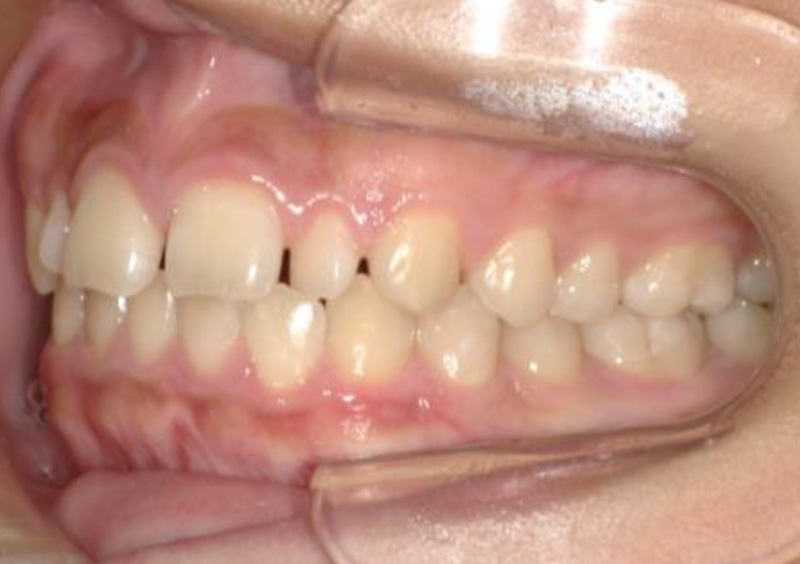

大人の矯正治療 歯に隙間がある(空隙歯列) 2025.10.24 【マルチブラケット矯正】隙間が気になる 治療前 治療後 担当医 一瀬 悠依華 先生 主訴 隙間が気になる。 期間 2年半 費用 65万円 治療内容 マルチブラケット装置 治療に伴うリスク 歯根吸収、歯肉退縮 関連症例